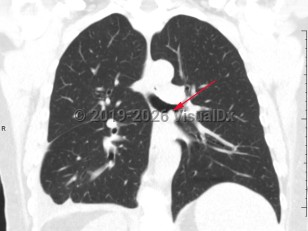

Fever, Cough, 50-59 year old Female

COVID-19